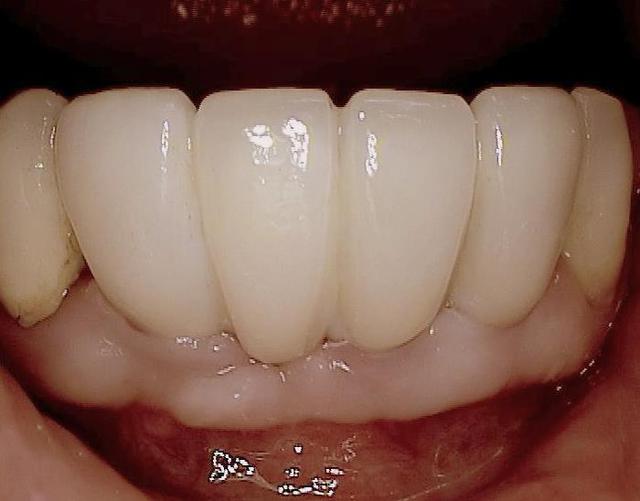

Sur la photo 14 (implants mandibulaires)

J'aime bien ce cas, sauf peut-être pour une certaine proximité des implants, car même si l'os peux être ok, pas facile pour la prothèse et son entretient.

ton commentaire m a fait remarqué que je n´ ai pas mis la photo de la prothèse du cas! merci ! :-)

ci dessous

Folie1 ofu0m9 - Eugenol

Folie2 z7edyr - Eugenol

Folie3 aeqhya - Eugenol

Folie4 q9egfx - Eugenol

Folie5 icxmia - Eugenol